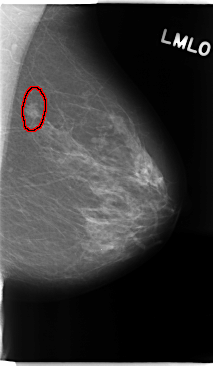

C_0135_1.LEFT_MLO

FILE: C_0135_1.LEFT_MLO.OVERLAY

TOTAL_ABNORMALITIES 1

ABNORMALITY 1

LESION_TYPE MASS SHAPE IRREGULAR MARGINS MICROLOBULATED

ASSESSMENT 4

SUBTLETY 5

PATHOLOGY MALIGNANT

TOTAL_OUTLINES 1

BOUNDARY